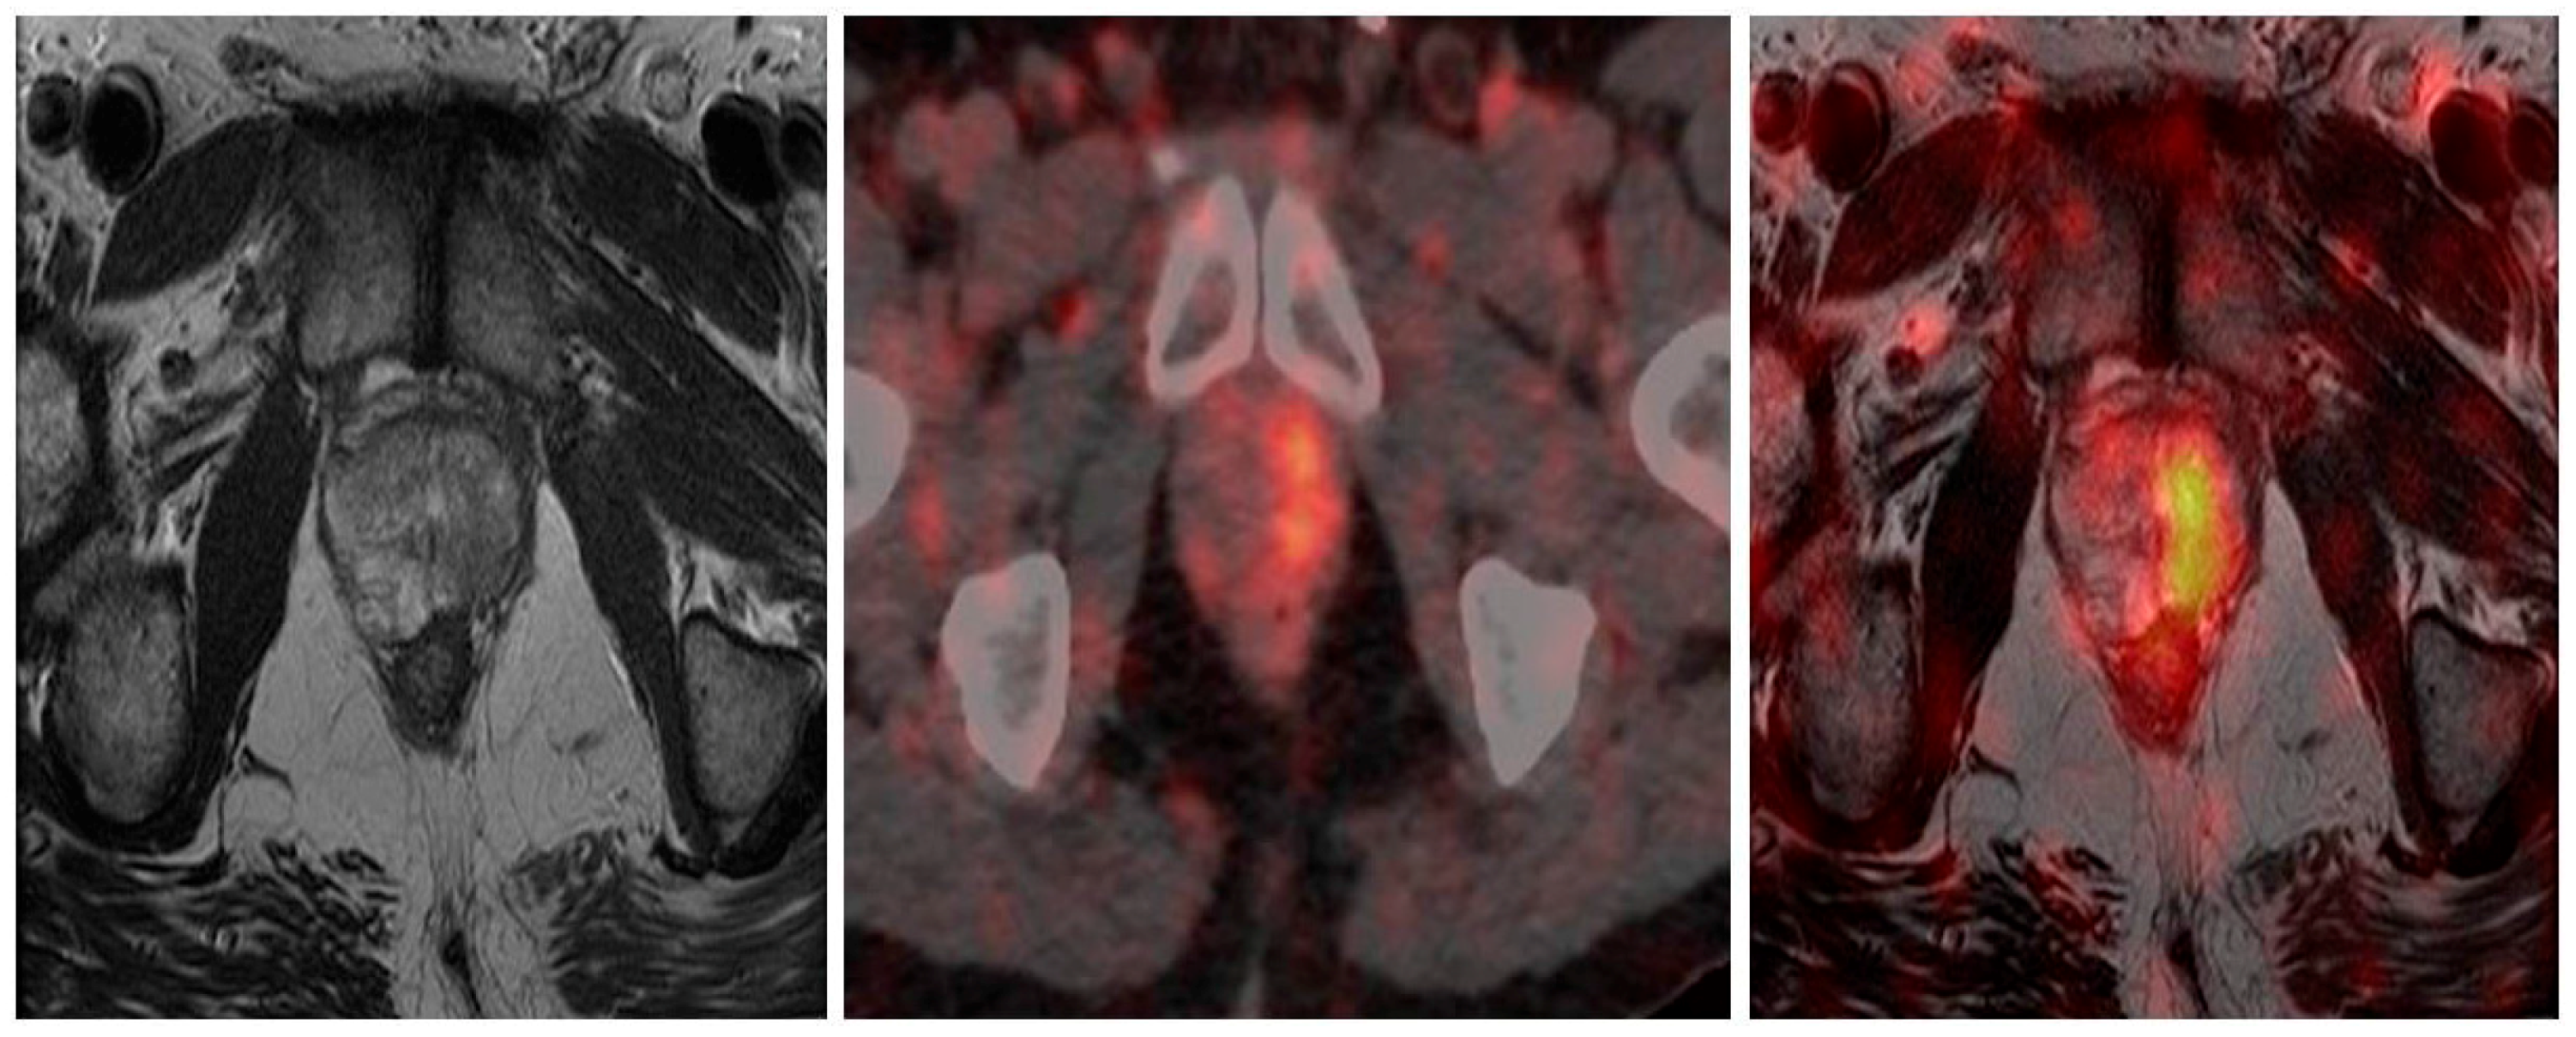

68Ga-PSMA PET/CT has recently been investigated as a potential staging modality in primary prostate cancer. Given that cellular PSMA expression has been shown to correlate with PSA and Gleason score [73] and 68Ga-PSMA PET/CT has been shown to be superior to standard staging modalities, such as CT, the use of 68Ga-PSMA PET/CT would seem to be a logical clinical extension in staging of primary disease. Early data appear to confirm this contention, with several studies [74,75], including our own [76], showing high rates of detection of CT occult early metastatic disease (Figure 2). In our recent study there was very good correlation between PSA and Gleason score and the chance of PSMA-avid metastatic disease. This finding correlates with other studies indicating a role in intermediate-to-high risk primary prostate cancer, with often occult nodal, and occasionally osseous, metastases identified. In assessment of potential bone metastases, 68Ga-PSMA PET/CT has been shown to be superior to bone scintigraphy in several studies [77,78].

Figure 2.

Staging 68Ga-PSMA PET/CT. Gleason 4 + 5. PSA 19 ng/mL. Intense 68Ga-PSMA avid primary disease in prostate with 68Ga-PSMA avid superficial left inguinal node metastasis.

The high sensitivity of 68Ga-PSMA PET/CT, coupled with the increased expression in higher grade tumors, guided intra-prostatic biopsy has shown in several small studies that 68Ga-PSMA avidity correlates well with gross tumor volume as detected by multiparametric MRI and voxel based determinants directly matched to histopathological specimens [81,82]. This correlation supports the concept of utilizing these data to potentially reduce sampling error and improve diagnostic accuracy of targeted biopsy. Current prostatic biopsy is often performed blind, although MRI directed biopsy based on Prostate Imaging Reporting and Data System (PI-RADS) is being increasingly utilized [83,84,85,86]. The addition of 68Ga-PSMA PET/MRI may further improve the utility and accuracy of this technique and direct biopsy to the most relevant area within the prostate. This is exquisitely demonstrated in Figure 3.

Figure 3.

Primary prostate cancer. PIRADS 4/5 left lobe of prostate on multiparametric MRI. Fused to 68Ga-PSMA PET/CT images for MRI in-bore guided targeted biopsy.